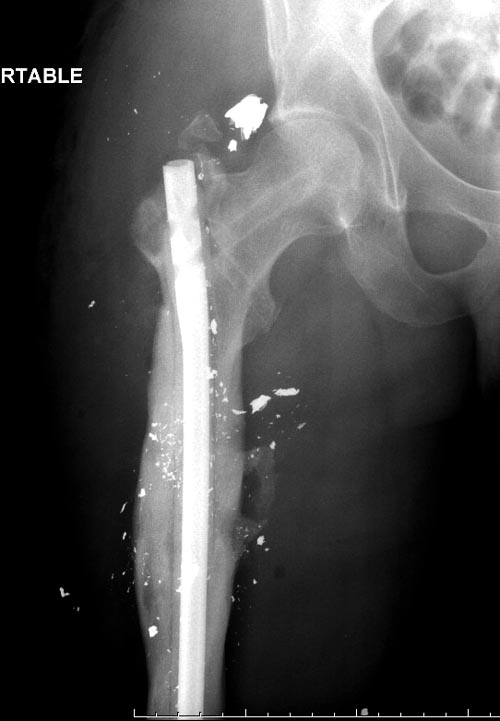

На снимках осложнение огнестрельного перелома бедра поздней инфекцией. 7

лет назад оперирован: правое бедро, сперва на ExFix, затем заменен на

гвоздь, а левая - гвоздь при поступлении.

Беспокойство проявил недавно, по поводу жалоб на боли сделано МРТ и

дренирование абсцесса терапевтами. Мы удалили гвоздь, сделали I&D,